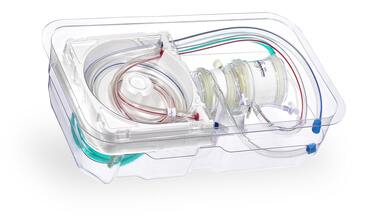

BioZone is a medical supplies company specializing in advanced, high-quality equipment and consumables for cardiac, vascular, electrophysiology (EP) surgeries, and other medical interventions. The company sources its products from leading global manufacturers and ensures they meet the needs of healthcare providers with the latest technology and innovation. BioZone focuses on offering equipment and consumables that enhance patient care, streamline surgical processes, and ensure procedural success.